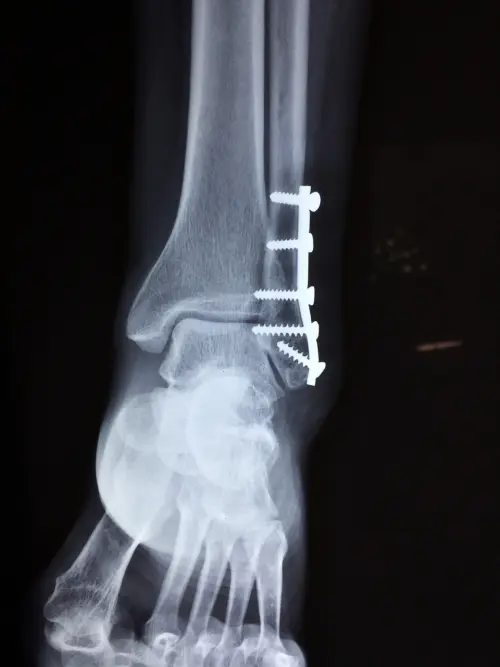

Interventi di chirurgia per malformazioni del piede

Tra gli altri problemi che potrebbero essere manifestati da un bambino, soprattutto a causa di problematiche legate alla gravidanza o al parto, si cita sicuramente il piede torto congenito. Si tratta di una condizione che comporta la distorsione o la rotazione anomala del piede di un neonato, per cui è essenziale intervenire immediatamente con interventi di chirurgia ortopedica, che permettono di garantire una corretta rotazione del piede, che ritornerà sul proprio asse, coinvolgendo anche tessuti e articolazioni.

Quella del piede torto non è l'unica malformazione che potrebbe essere presente in un bambino, dal momento che esistono anche altre malformazioni del piede, per cui si richiede l'intervento della chirurgia ortopedica per la correzione di tali problematiche. In genere, l'ortopedia è essenziale per correggere i problemi di simmetria, rotazione e posizionamento del piede, per garantirne un ottimo sviluppo, soprattutto negli anni del movimento e dei primi passi.